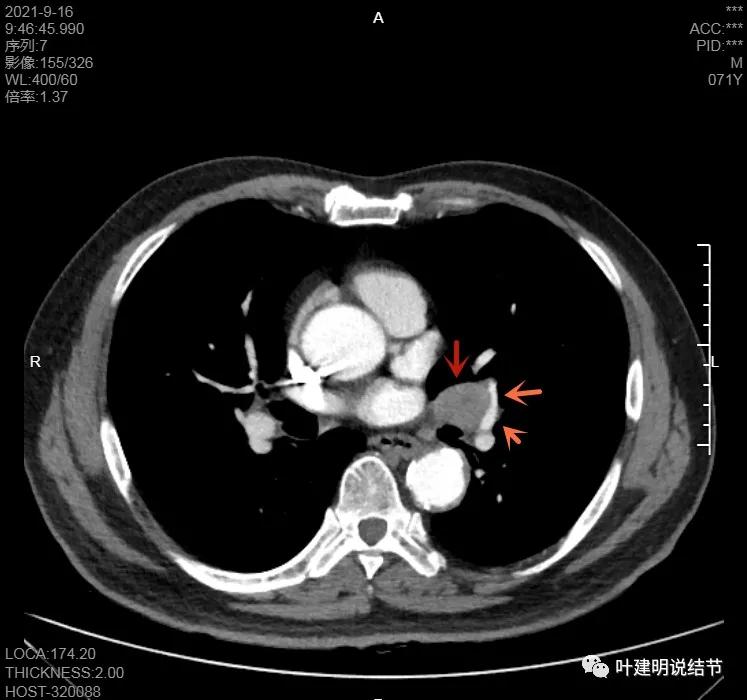

左肺门区淋巴结肿大

肺门区淋巴结挤压附近肺血管,但似乎示见肿瘤侵犯破坏血管壁